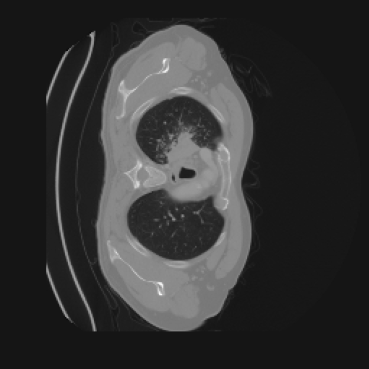

As shown in Figure 5, the generated slices exhibit high consistency across adjacent slices. The anatomical structures and semantic patterns are smoothly and coherently preserved between slices, indicating that our model is capable of generating 3D-consistent synthetic images rather than isolated 2D slices.

Figure 8 further supports these findings: the images generated by Med-LSDM preserve spatial coherence across coronal and sagittal planes, whereas those from SegGuidedDiff show noticeable inconsistencies. These artifacts likely result from the 2D nature of SegGuidedDiff, which fails to account for 3D spatial relationships. In contrast, our model’s volumetric diffusion framework inherently preserves anatomical consistency, highlighting its advanta in synthesizing high-fidelity 3D medical images.

To demonstrate the advantages of 3D semantic image synthesis over 2D semantic semantic image synthesis, we conducted a detailed comparison with the SegGuidedDiff [26] model. SegGuidedDiff generates medical images based on 2D semantic maps, producing individual 2D slices that are later stacked to form a 3D image. However, this approach has limitations in capturing spatial continuity and coherence across slices, which is critical for representing the spatial structure of 3D medical images. As a result, inconsistencies often arise between different slices, particularly in preserving anatomical structures across the coronal and sagittal planes. The generated images exhibit varying levels of denoising, resulting in differences in brightness and sharpness across the images. This inconsistency in denoising can lead to noticeable variations in visual quality, where some regions appear clearer and others less distinct.

The motivation for this work arises from the need to address these limitations in the synthesis of 3D medical images. Current techniques do not produce high-resolution 3D images that preserve spatial coherence and capture the full complexity of medical data, as shown in Figure 2, 5. The development of advanced 3D generative models tailored specifically for medical imaging could not only improve the quality of synthetic medical images but also help alleviate data scarcity, enhance privacy protection, reduce computational requirement and ultimately advance the use of deep learning in healthcare applications.